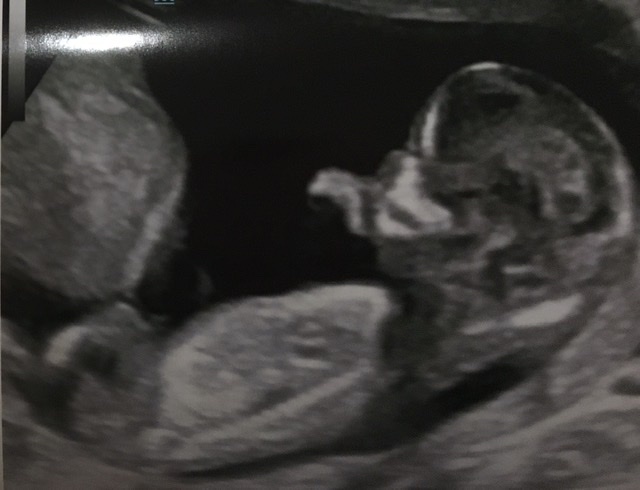

Hi, this is the best image from my scan yesterday. During scan I thought I saw nub - long bright white line - but couldn’t work out angle. Unfortunately, it’s not in the picture - but I wondered if the two tiny lines circled might be the end of it poking out? If so, could anyone hazard a guess as to sex? Thanks in advance!